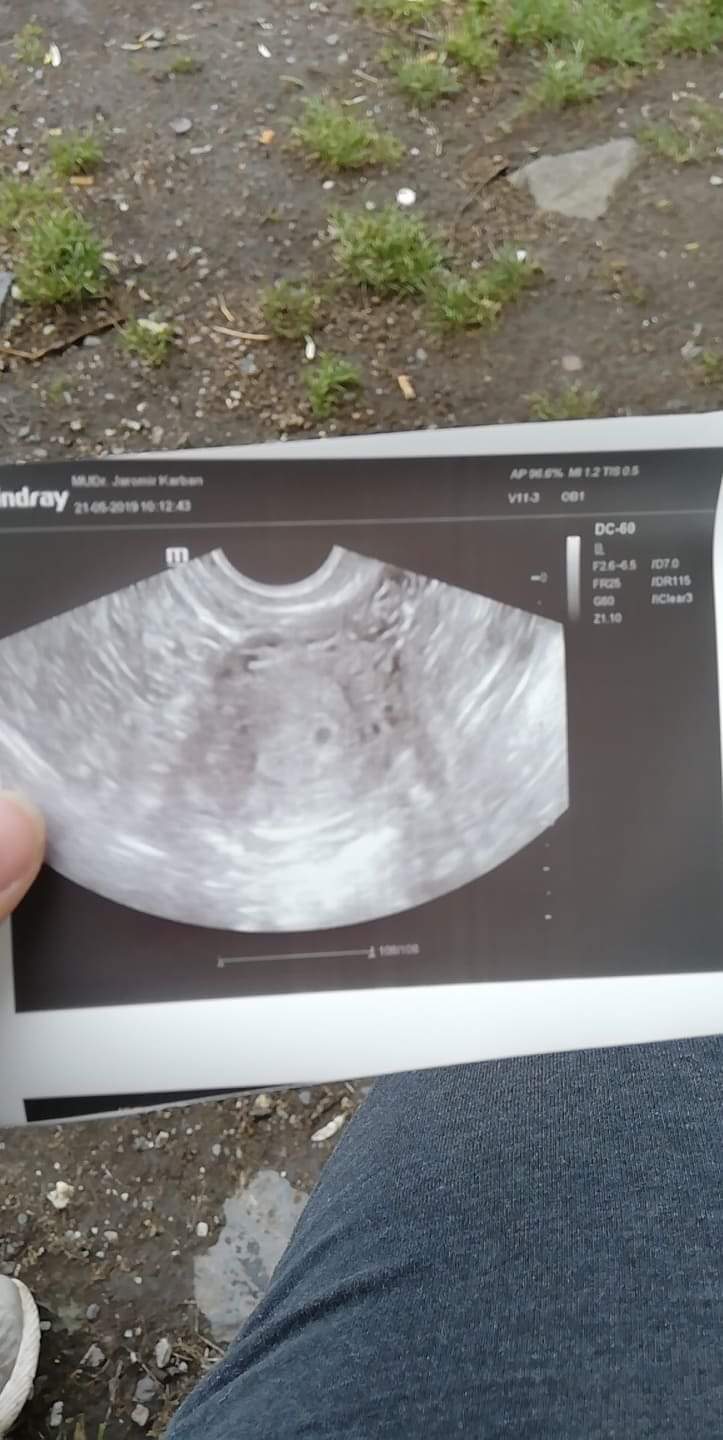

Ahoj holky.Kdyz jsem byla na utz v 5+5tt tak byla videt jen pidi midi tecka.na ko jdu pristi tyden.mate nektera foto utz z 5+5 a 4+5 na porovnani?